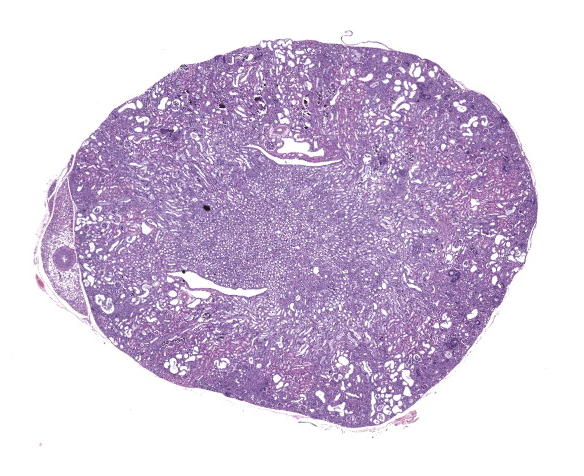

Kidney. The surface of the renal cortex is undulating with an irregular, scalloped appearance. Multifocally, renal tubules are dilated and have an attenuated epithelium. Dilated tubules are variably filled with an amorphous, pale basophilic material or abundant degenerate neutrophils, and less commonly contain brown to pale basophilic, spiculated, radiating birefringent crystalline material (2,8-dihydroxyadenine crystals) or dark basophilic coarsely granular material. Occasionally, crystal-filled tubules are surrounded by neutrophils, macrophages, and multinucleated giant cells. Often, Bowman’s spaces are mild to moderately dilated. Throughout the renal parenchyma, between tubules are streams of fibroblasts and collagen.

Kidney, cortex: Tubular degeneration, necrosis, and regeneration, chronic, diffuse, marked, with intratubular and interstitial crystals, granular and hyaline casts, mineralization, and interstitial fibrosis.